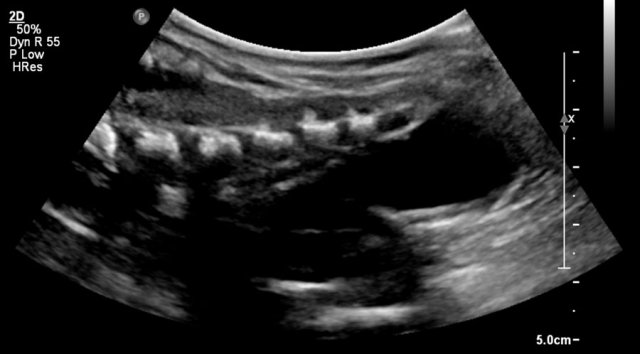

Here an ultrasound image of a five-month-old boy with an antenatally detected dilated pyelocalyceal system and no visible ureter, in accordance with a ureteropelvic junction stenosis.

On a sagittal image the dilated pyelocalyceal system is well seen.